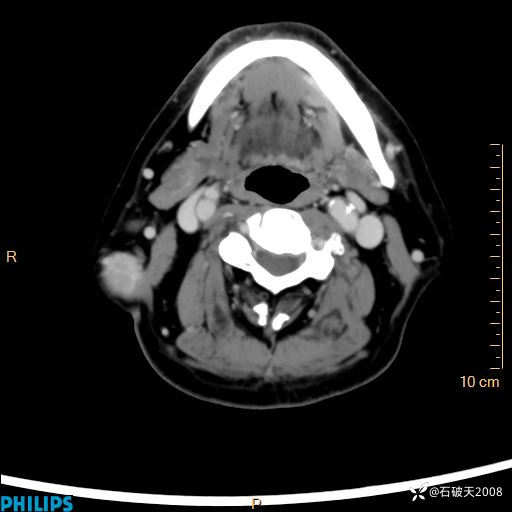

病例分享:颈部占位,一周后公布病理

男 57岁 主 诉:发现右侧颌下肿物1月余。

现病史:1月余前家属发现右侧颌下肿物。局部皮肤无红肿、热痛,无吞咽困难,无异物感,无恶心、呕吐,无头痛、头晕,无胸闷、胸痛,无发热、咳嗽、咳痰及呼吸困难。于我院行体表肿块彩超检查(2024.03.15我院)示:右侧耳下皮下软组织内低回声,未治疗。今为进一步治疗门诊以“腮腺肿瘤”为诊断收住我科,发病来患者神志清,精神可,饮食、睡眠及大小便正常,体重无明显下降。

静脉期